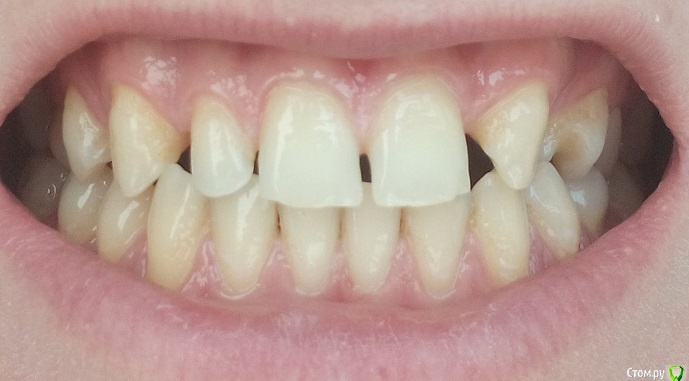

sergemiko Опубликовано 20 февраля, 2018 Поделиться Опубликовано 20 февраля, 2018 (изменено) Добрый день. Планирую ставить брекеты (на 2 года, самому 27 лет, муж.), но для полной красоты не хватает 12 зуба. Врач предложил сместить брекетами зубы друг к другу, либо, наоборот, раздвинуть для импланта на место отсутствующего 22 и коронки под 12 зуб. Вот, хочу посоветоваться, как лучше поступить.18 и 28 зубы уже удалены, собственно, я думаю, именно они, прорезываясь, сместили зубы в кривизну, но брекеты я решил ставить ещё до этого.37 зуб сделал доп.снимок, который показал, что воспаление не ярко выражено как на панорамном снимке, решили его не трогать.PS: немного смущают дёсна, кажется что оголились или это норма? Изменено 20 февраля, 2018 пользователем sergemiko Ссылка на комментарий

Дмитрий Л. Опубликовано 20 февраля, 2018 Поделиться Опубликовано 20 февраля, 2018 Вы наверное запутались с номерами зубов.Имплант лучше ставить подальше. Если есть возможность сместить ваш левый клык вперёд и запротезировать его под резец, а на место сдвинутого клыка поставить имплантат, то лучше делать так. В идеале фронт под виниры. По фото судить трудно, вашем врачу виднее ситуация. Ссылка на комментарий

sergemiko Опубликовано 20 февраля, 2018 Автор Поделиться Опубликовано 20 февраля, 2018 Вы наверное запутались с номерами зубов.Имплант лучше ставить подальше. Если есть возможность сместить ваш левый клык вперёд и запротезировать его под резец, а на место сдвинутого клыка поставить имплантат, то лучше делать так. В идеале фронт под виниры. По фото судить трудно, вашем врачу виднее ситуация.Да, перепутал, не хватает 22 зуба, а не 12. А почему именно левый клык сместить вперёд и запротезировать его под резец, а на место сдвинутого клыка поставить имплантат, а не поставить резец-имплантат, сместив клык назад или не принципиально важно? Ведь с правой стороны резец есть. И, кстати, на правый резец ставится коронка или винир? Ссылка на комментарий

Дмитрий Л. Опубликовано 20 февраля, 2018 Поделиться Опубликовано 20 февраля, 2018 Да, перепутал, не хватает 22 зуба, а не 12. А почему именно левый клык сместить вперёд и запротезировать его под резец, а на место сдвинутого клыка поставить имплантат, а не поставить резец-имплантат, сместив клык назад или не принципиально важно? Ведь с правой стороны резец есть. И, кстати, на правый резец ставится коронка или винир?На родном зубе проще добиться эстетики. На правый резец скорее всего коронка, но это не важно, коронка и винир одинаково эстетичны и изготавливаются из одних и тех же материалов.И снова, вашему врачу виднее как лучше. Ссылка на комментарий

Bier Опубликовано 22 февраля, 2018 Поделиться Опубликовано 22 февраля, 2018 Я бы все же ставил клык на свое место и имплантировал резец. Условия хорошие, если нормально сделать, все получится. 1 Ссылка на комментарий